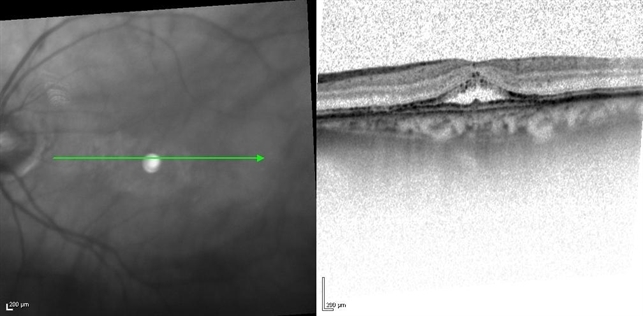

- Bulls eye maculopathy of unknown etiology

- bull's eye maculopathy, optical coherence tomography (OCT), chronic central serous chorioretinopathy (CSCR)

- 75-YEAR-OLD FEMALE PRESENTS WITH BILATERAL GRADUAL VISUAL LOSS 6/30 Dx BE PSEUDOPHAKIA + PCO BE BULLS EYE MACULOPATHY PER FA VA IMPROVES TO 6/10 S/P YAG CAPSULOTOMY OCT - BE MACULAR SUBRETINAL FLUID NO HISTORY OF CHLOROQUINE THERAPY NO DRUSEN OR SIGNS OF AMD WORKING DIAGNOSIS - BE CHRONIC CSCR